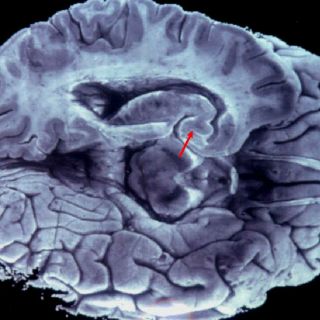

WASHINGTON, ESTADOS UNIDOS (12/AGO/2013).- El cerebro agonizante de ratas de laboratorio exhibe actividades características de la percepción consciente, en un estudio que aparentemente valida las "experiencias cercanas a la muerte" de la que hablan los sobrevivientes de fallo cardíaco, según un estudio hoy en Proceedings of the National Academy of Sciences.

Un estudio de la Universidad de Michigan (UM) muestra que poco después de la muerte clínica, que ocurre cuando el corazón deja de latir y la sangre deja de fluir al cerebro, las ratas exhiben patrones de actividad cerebral característicos de la percepción consciente.